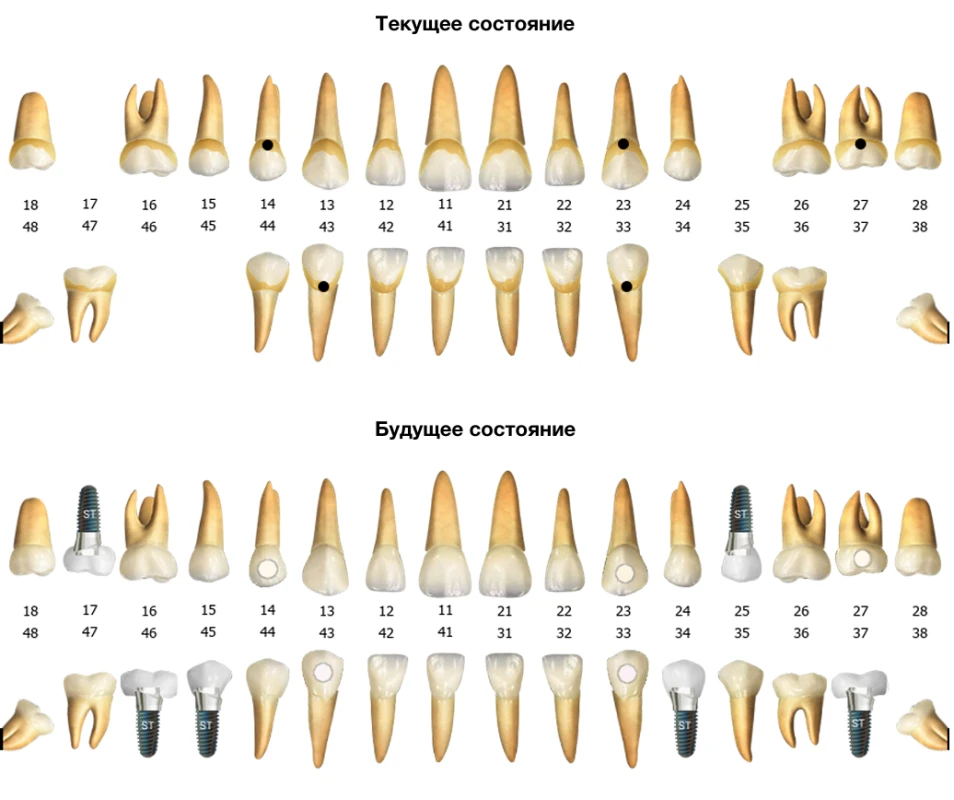

- Электронные карты пациентов: Хранение полной информации о пациентах, включая историю заболеваний, результаты анализов и планы лечения.

| Электронная медицинская карта пациента | да |

| Зубная формула (стом.карта) | да |